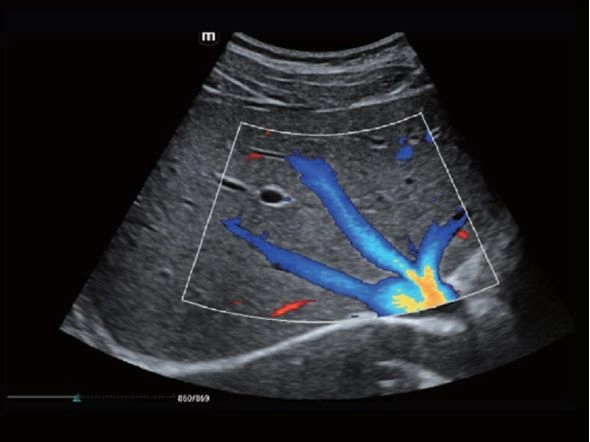

Сонная артерия и яремная вена

Пенченочная вена